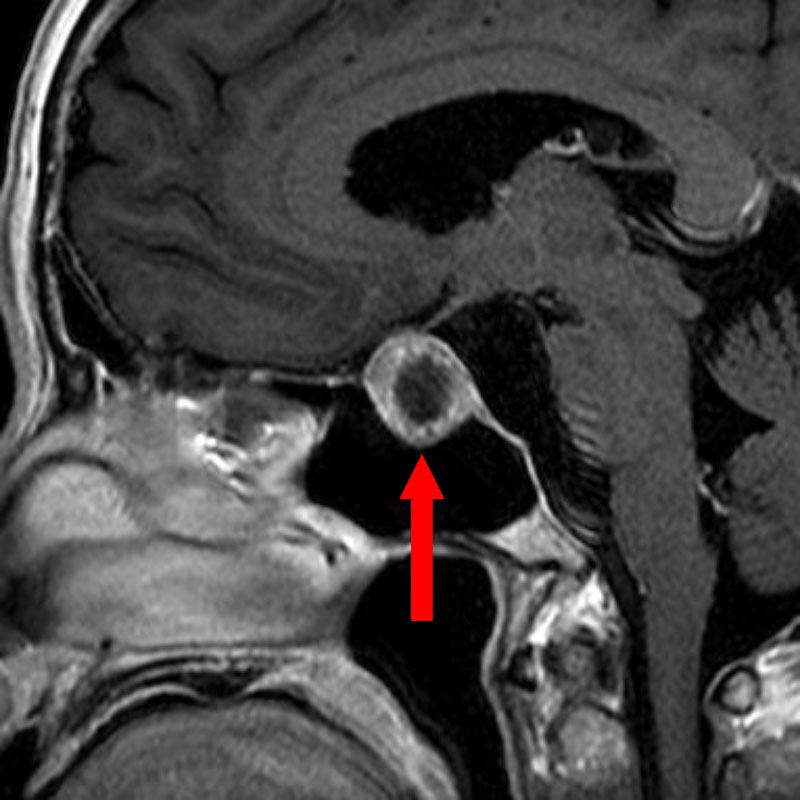

No.’25_44 手術前1

No.’25_44 手術前2

No.’25_44 摘出 前

No.’25_44  摘出 中

No.’25_44 摘出 後